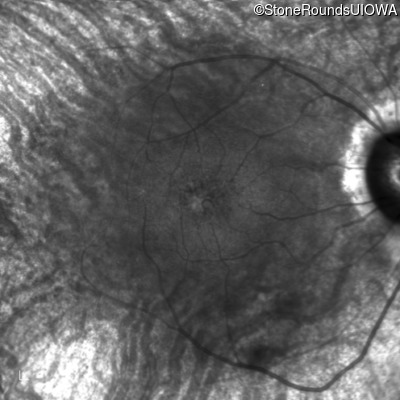

Age at visit: 49 years (Visit 2)